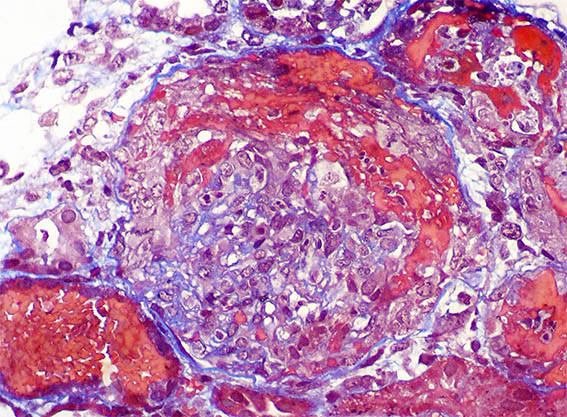

Figure 1.

H&E, X100.